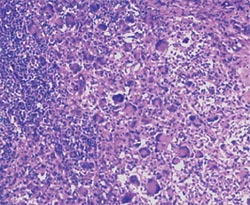

2. Présence de lésions microscopiques caractéristiques dans les organes lymphoïdes : le rapport d’histologie du laboratoire d’analyses mentionne alors une déplétion lymphocytaire avec infiltration histiocytaire (granulomateuse). Il y a une présence variable de cellules géantes multinucléées (au milieu des années 90, ce critère était considéré comme essentiel ; depuis, il n’est que secondaire). La présence d’inclusions intracytoplasmiques est fréquente (si une technique additionnelle est mise en œuvre, il est possible d’observer que ces agrégats contiennent du PCV2).

3. Détection de PCV2 dans les lésions des tissus lymphoïdes typiques (point 2), chez cet animal (point 1), par une technique qui permet d’estimer la quantité de PCV2 (ses protéines, par immunomarquage, ou son génome, par hybridation in situ), et de l’associer à l’intensité des lésions.